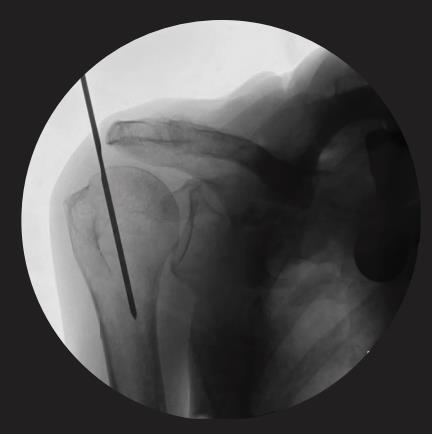

• Entry point

• central entry point

• located at the very top of the humeral head, in the articular surface, in line with humeral axis

• guide wire

• insert the ball tip guide wire 2.5 x 800mm

• advance the Ball Tip Guide Wire through the fracture site and to the desired insertion depth

• depth of insertion may be visualized with the aid of fluoroscopy

• to perform guided distal locking, it is essential to place the X-ray beam of a C-arm approximately 30° oblique to the axis of the drill sleeve assembly

• once the C-arm has been adjusted so that nail and sleeve are shown in parallel, the deviated image will show the sleeve either medial or lateral to the nail

• if the sleeve and the nail are shown parallel and collinear no further adjustment of the sleeve is needed

• if the sleeve and nail tip are not seen on the same axis, sleeve adjustment is required by turning the knob of the Distal Targeting Device